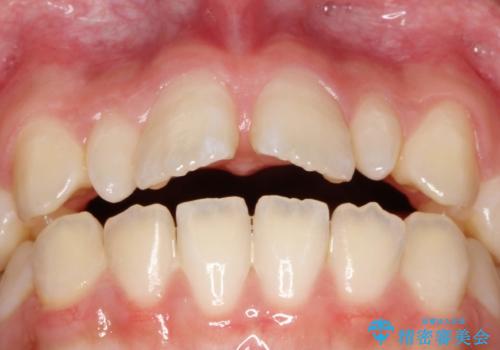

上あごの2番目の歯は矮小歯といって、生まれつき小さい歯となる事がよくあります。

このような場合、矯正によりスペースを集め、本来あるべき形態にセラミックで修正することもできます。

時間はかかりましたが、きれいな笑顔になりました。

かぶせ物の種類:PFZ standard